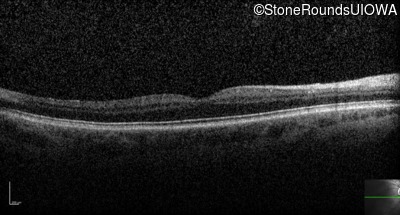

The clinical features supporting the diagnosis of congenital stationary synaptic dysfunction in this patient include: nystagmus noticed in the first year of life; reduced acuity; normal color naming; a normal fundus appearance; a normal OCT; selective loss of the b-wave on the scotopic bright flash ERG; normally sighted parents; and, a similarly affected maternal grandfather and maternal male cousin.